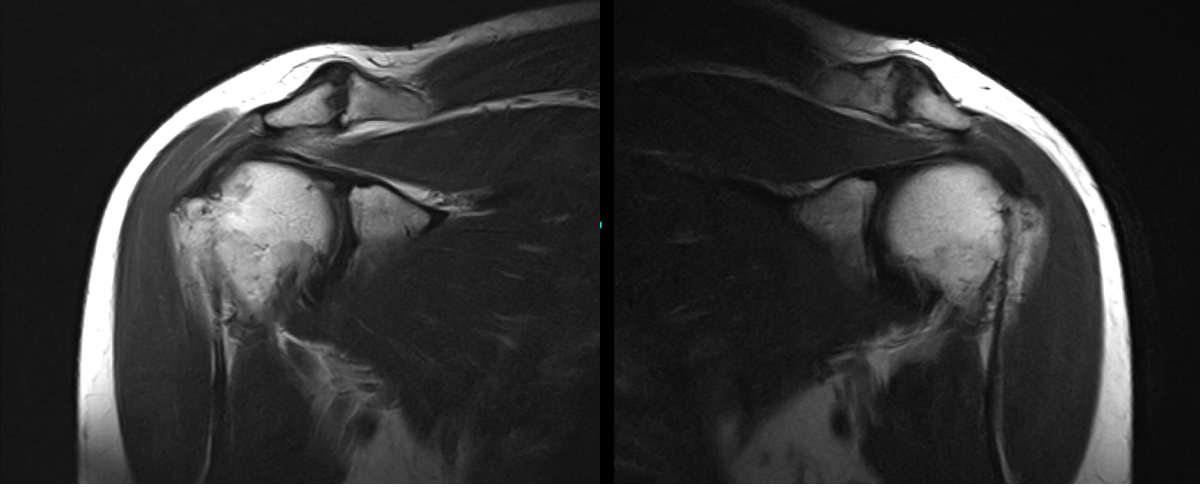

The patient presented MRI results for both shoulders. For the right, low-grade interstitial tear of the posterior supraspinatus tendon. Mild supraspinatus and subscapularis tendinosis.

For the left, A low grade interstitial tear of the posterior supraspinatus tendon on mild background tendinosis. Tearing of the posterior-superior labrum. Mild acromioclavicular joint osteoarthritis.

MRI Left Shoulder Non-contrast